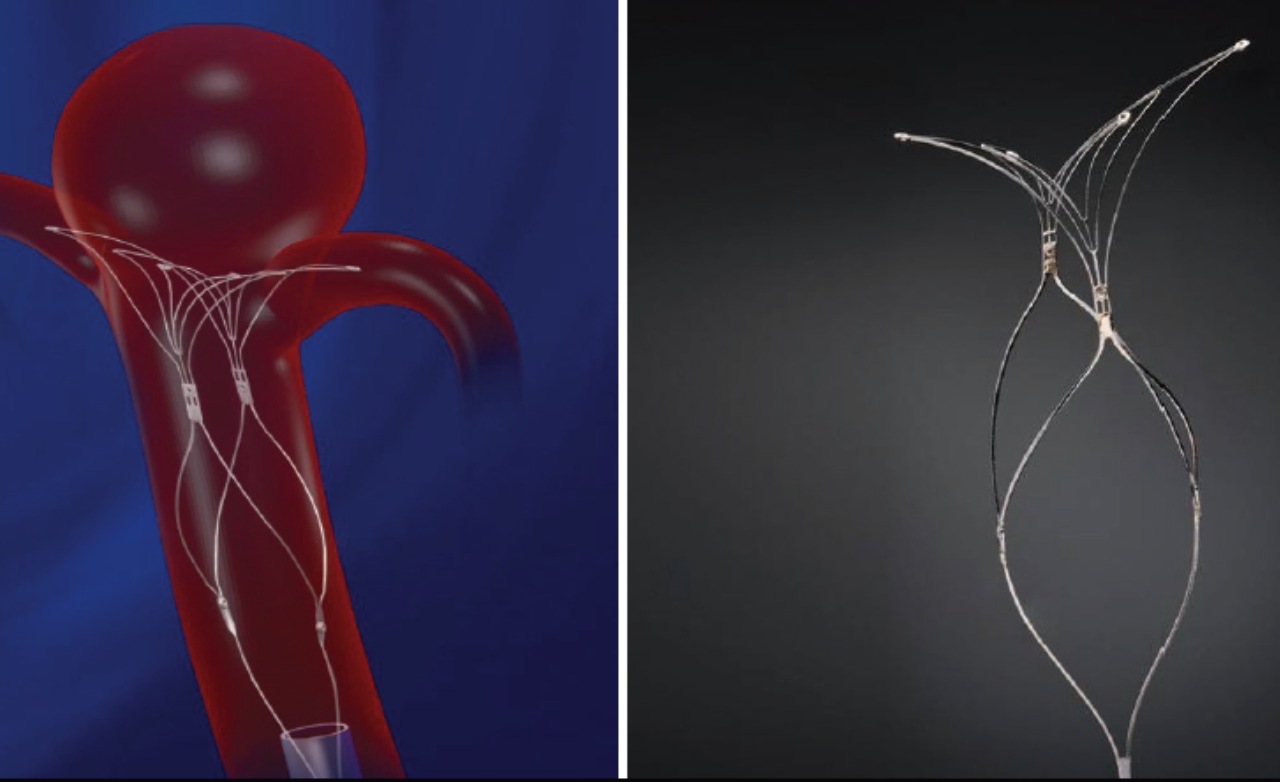

A bulging, weakened blood vessel in the brain that may rupture, causing life-threatening bleeding, headaches, neurological deficits, or stroke.

Enhances treatment by redirecting blood flow away from the aneurysm, promoting gradual healing, improving vessel stability, and ensuring stronger, durable protection against future rupture.

Placed directly inside the aneurysm sac, these devices offer targeted treatment with minimal vessel manipulation for improved safety.